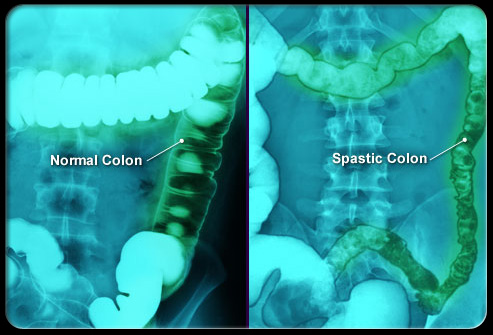

肠易激惹综合征 (IBS)

盆腔疼痛怎么引起的,盆腔疼痛是什么原因引起的

盆腔和腹部疼痛、胀气、时不时出现的便秘或腹泻通常是肠易激惹综合征(IBS)造成的。IBS是一种伴有反复发作症状的慢性功能性疾病。IBS的治疗包括调整饮食、管理压力和用药。